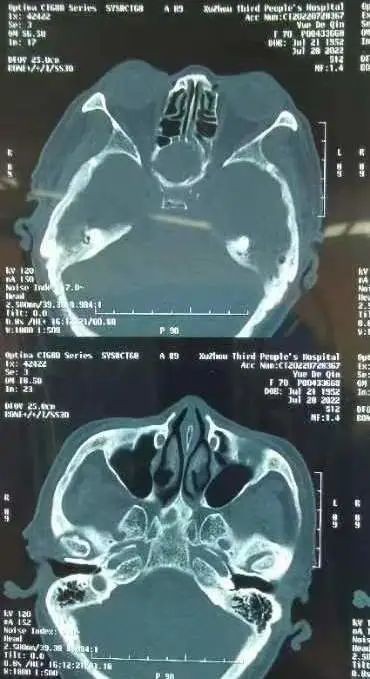

術(shù)前術(shù)后CT對(duì)比

“由于蝶竇位置特殊,位居顱底深部,與垂體、頸內(nèi)動(dòng)脈、視神經(jīng)等重要結(jié)構(gòu)緊密相連,一旦損傷頸內(nèi)動(dòng)脈,將導(dǎo)致大出血,損傷視神經(jīng)則可能造成不可逆的失明。其次,這個(gè)病例具有迷惑性,膿囊腫壓迫的是右側(cè)蝶竇,正常來(lái)說(shuō)是右眼無(wú)光感,但實(shí)際上是左側(cè)視力失明,鼻竇CT雖然能看到占位,但是看不到蝶竇膿囊腫侵蝕破壞的地方。”王浩臨危不亂,在鼻內(nèi)鏡下精細(xì)操作,探查發(fā)現(xiàn),由于右側(cè)巨大腫物擊穿蝶竇間隔進(jìn)而造成左側(cè)視神經(jīng)管受損而導(dǎo)致左眼失明,手術(shù)全程順利,術(shù)后予以抗感染、止血等治療,岳老太頭痛等癥狀消失,左眼復(fù)明。一周后出院時(shí)向耳鼻喉科醫(yī)護(hù)人員豎起了大拇指,為他們精湛的醫(yī)術(shù)與貼心的護(hù)理服務(wù)點(diǎn)贊。